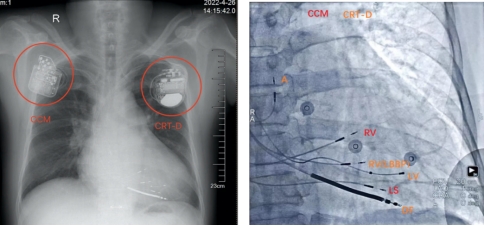

术中分别对CRT-D及CCM进行参数测试

经过术前缜密的准备,手术如期举行。手术在于波指导下进行,局麻下李述峰带领曹威及李宁进行手术,因为术前充分准备,手术过程按原定的计划进行,电极植入、位置确认、参数测试(包括避免与CRT-D发生无感知等)、参数设定、电极固定缝合,团队历时1个多小时顺利完成手术。

术后影像,CCM成功植入